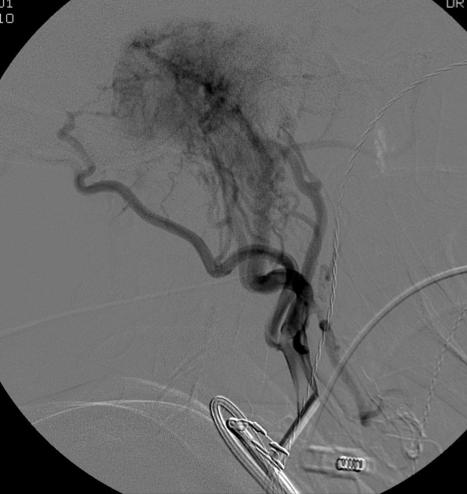

An investigation for pulsatile tinnitus